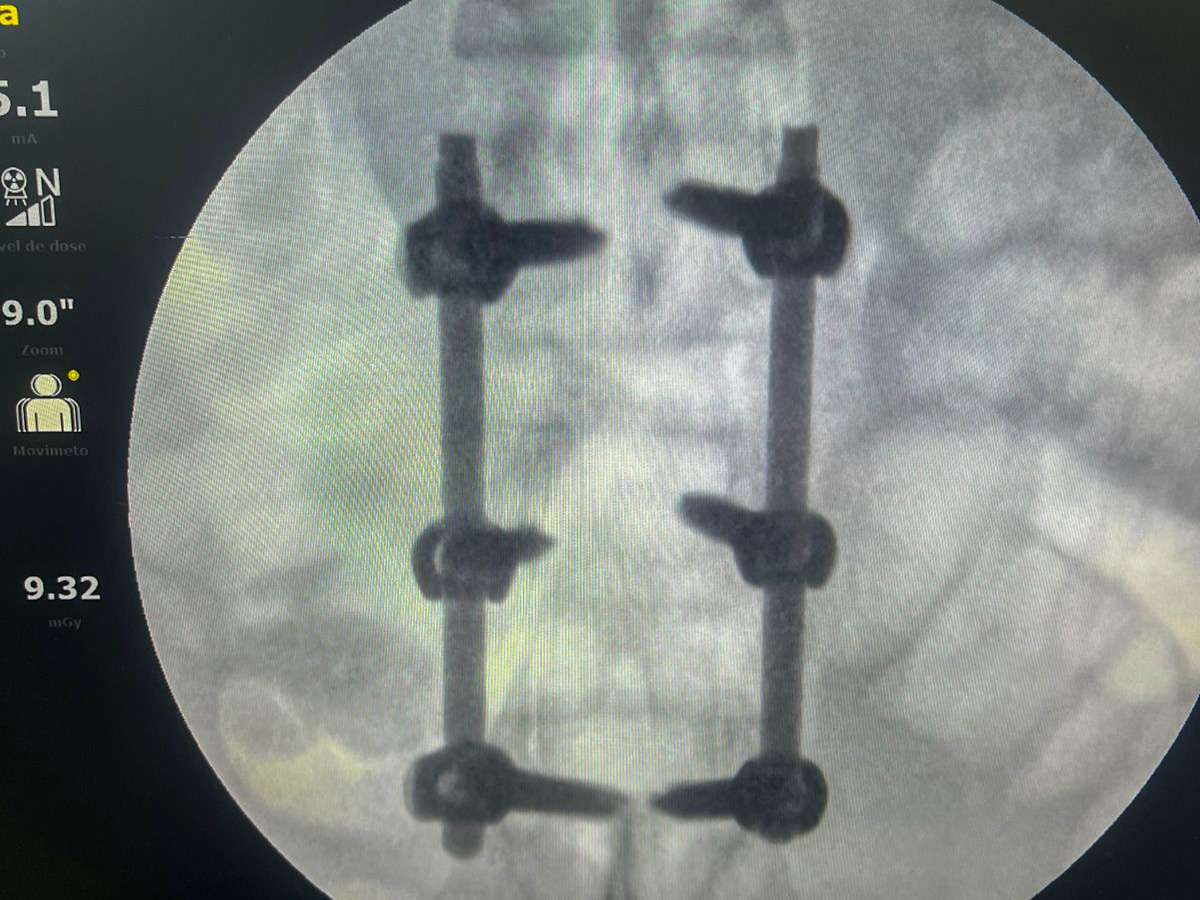

O procedimento, que durou 1h45, foi conduzido pelos ortopedistas especialistas em coluna, doutor Marlon Mendonça e Paulo Splenger, com apoio da equipe de trauma da unidade. Segundo o médico, a cirurgia transcorreu com sucesso e sem intercorrências. “O paciente chegou lúcido à UTI e já estava conversando após o procedimento. A expectativa agora é acompanhar a evolução neurológica, que depende do tempo e da resposta do organismo”, explicou doutor Marlon.

A intervenção teve como objetivo a descompressão da medula e a estabilização da coluna, medidas urgentes para minimizar os danos causados pelo trauma. “É um marco. Iniciamos um novo capítulo para o hospital, com a realização de cirurgias de alta complexidade que antes não eram possíveis. Isso representa mais qualidade, mais dignidade e menos sofrimento para os nossos pacientes”, afirmou doutor Paulo Splenger.